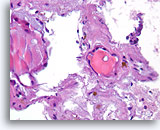

Afbeelding 68

Papillair schildkliercarcinoom, schildklier FNA, celblok.

Zowel papillaire schildkliercarcinomen en benigne hyperplastische nodulen kunnen papillaire structuren bevatten. De opeenstapeling van de kernen doet een papillair schildkliercarcinoom vermoeden.

20X

Afbeelding 68

Papillair schildkliercarcinoom, schildklier FNA, celblok.

Zowel papillaire schildkliercarcinomen en benigne hyperplastische nodulen kunnen papillaire structuren bevatten. De opeenstapeling van de kernen doet een papillair schildkliercarcinoom vermoeden.

20X

Afbeelding 69

Papillair schildkliercarcinoom, schildklier FNA, celblok.

Een sterkere vergroting van afbeelding 68 toont diagnostische kenmerken van opeengestapelde kernen met nucleaire groeven, erg fijne chromatine, een zeldzame intranucleaire cytoplasmische inclusie (open pijl) en hier en daar een nauwelijks merkbaar verlies aan polariteit.

60X

Afbeelding 69

Papillair schildkliercarcinoom, schildklier FNA, celblok.

Een sterkere vergroting van afbeelding 68 toont diagnostische kenmerken van opeengestapelde kernen met nucleaire groeven, erg fijne chromatine, een zeldzame intranucleaire cytoplasmische inclusie (open pijl) en hier en daar een nauwelijks merkbaar verlies aan polariteit.

60X